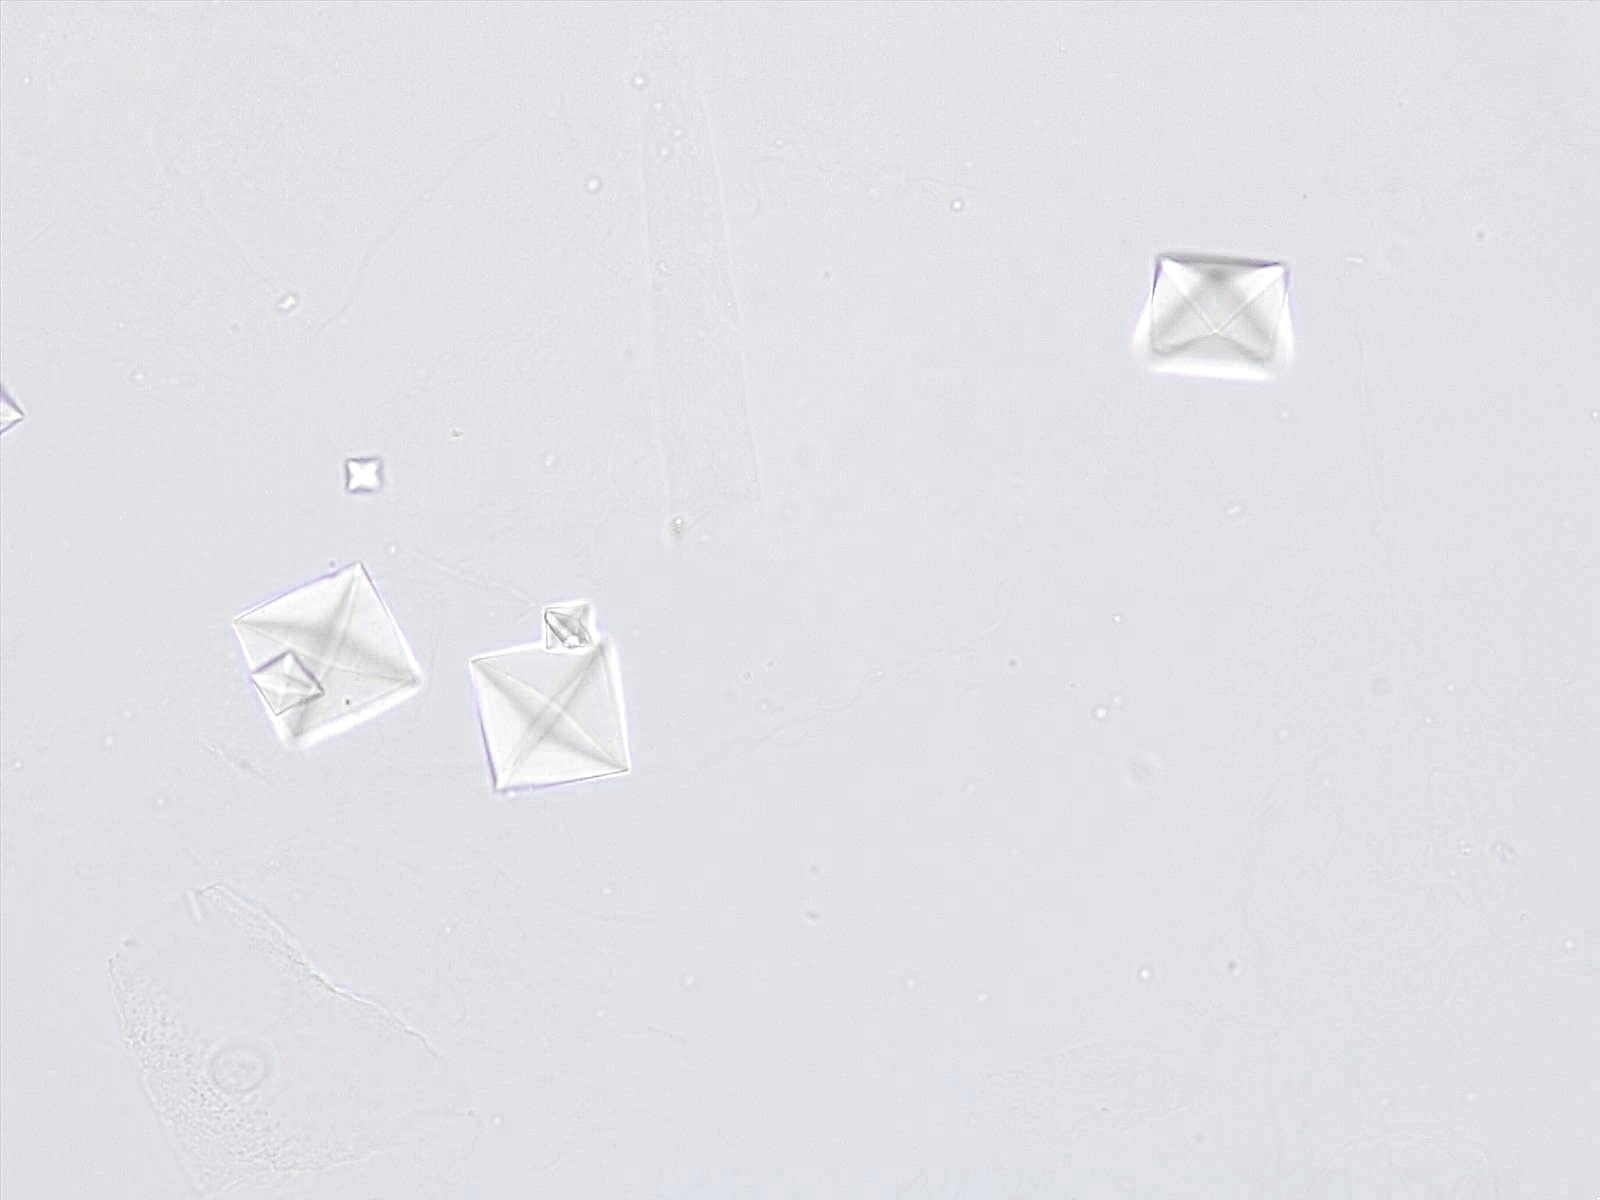

Calciumoxalaat dihydraat kristallen hebben karakteristieke bipyramidale of prismatische vormen. Onder de microscoop verschijnen ze vaak als envelop-vormige structuren, met een duidelijke en symmetrische morfologie. De grootte van de kristallen kan sterk variëren.

Individueel

Techniek